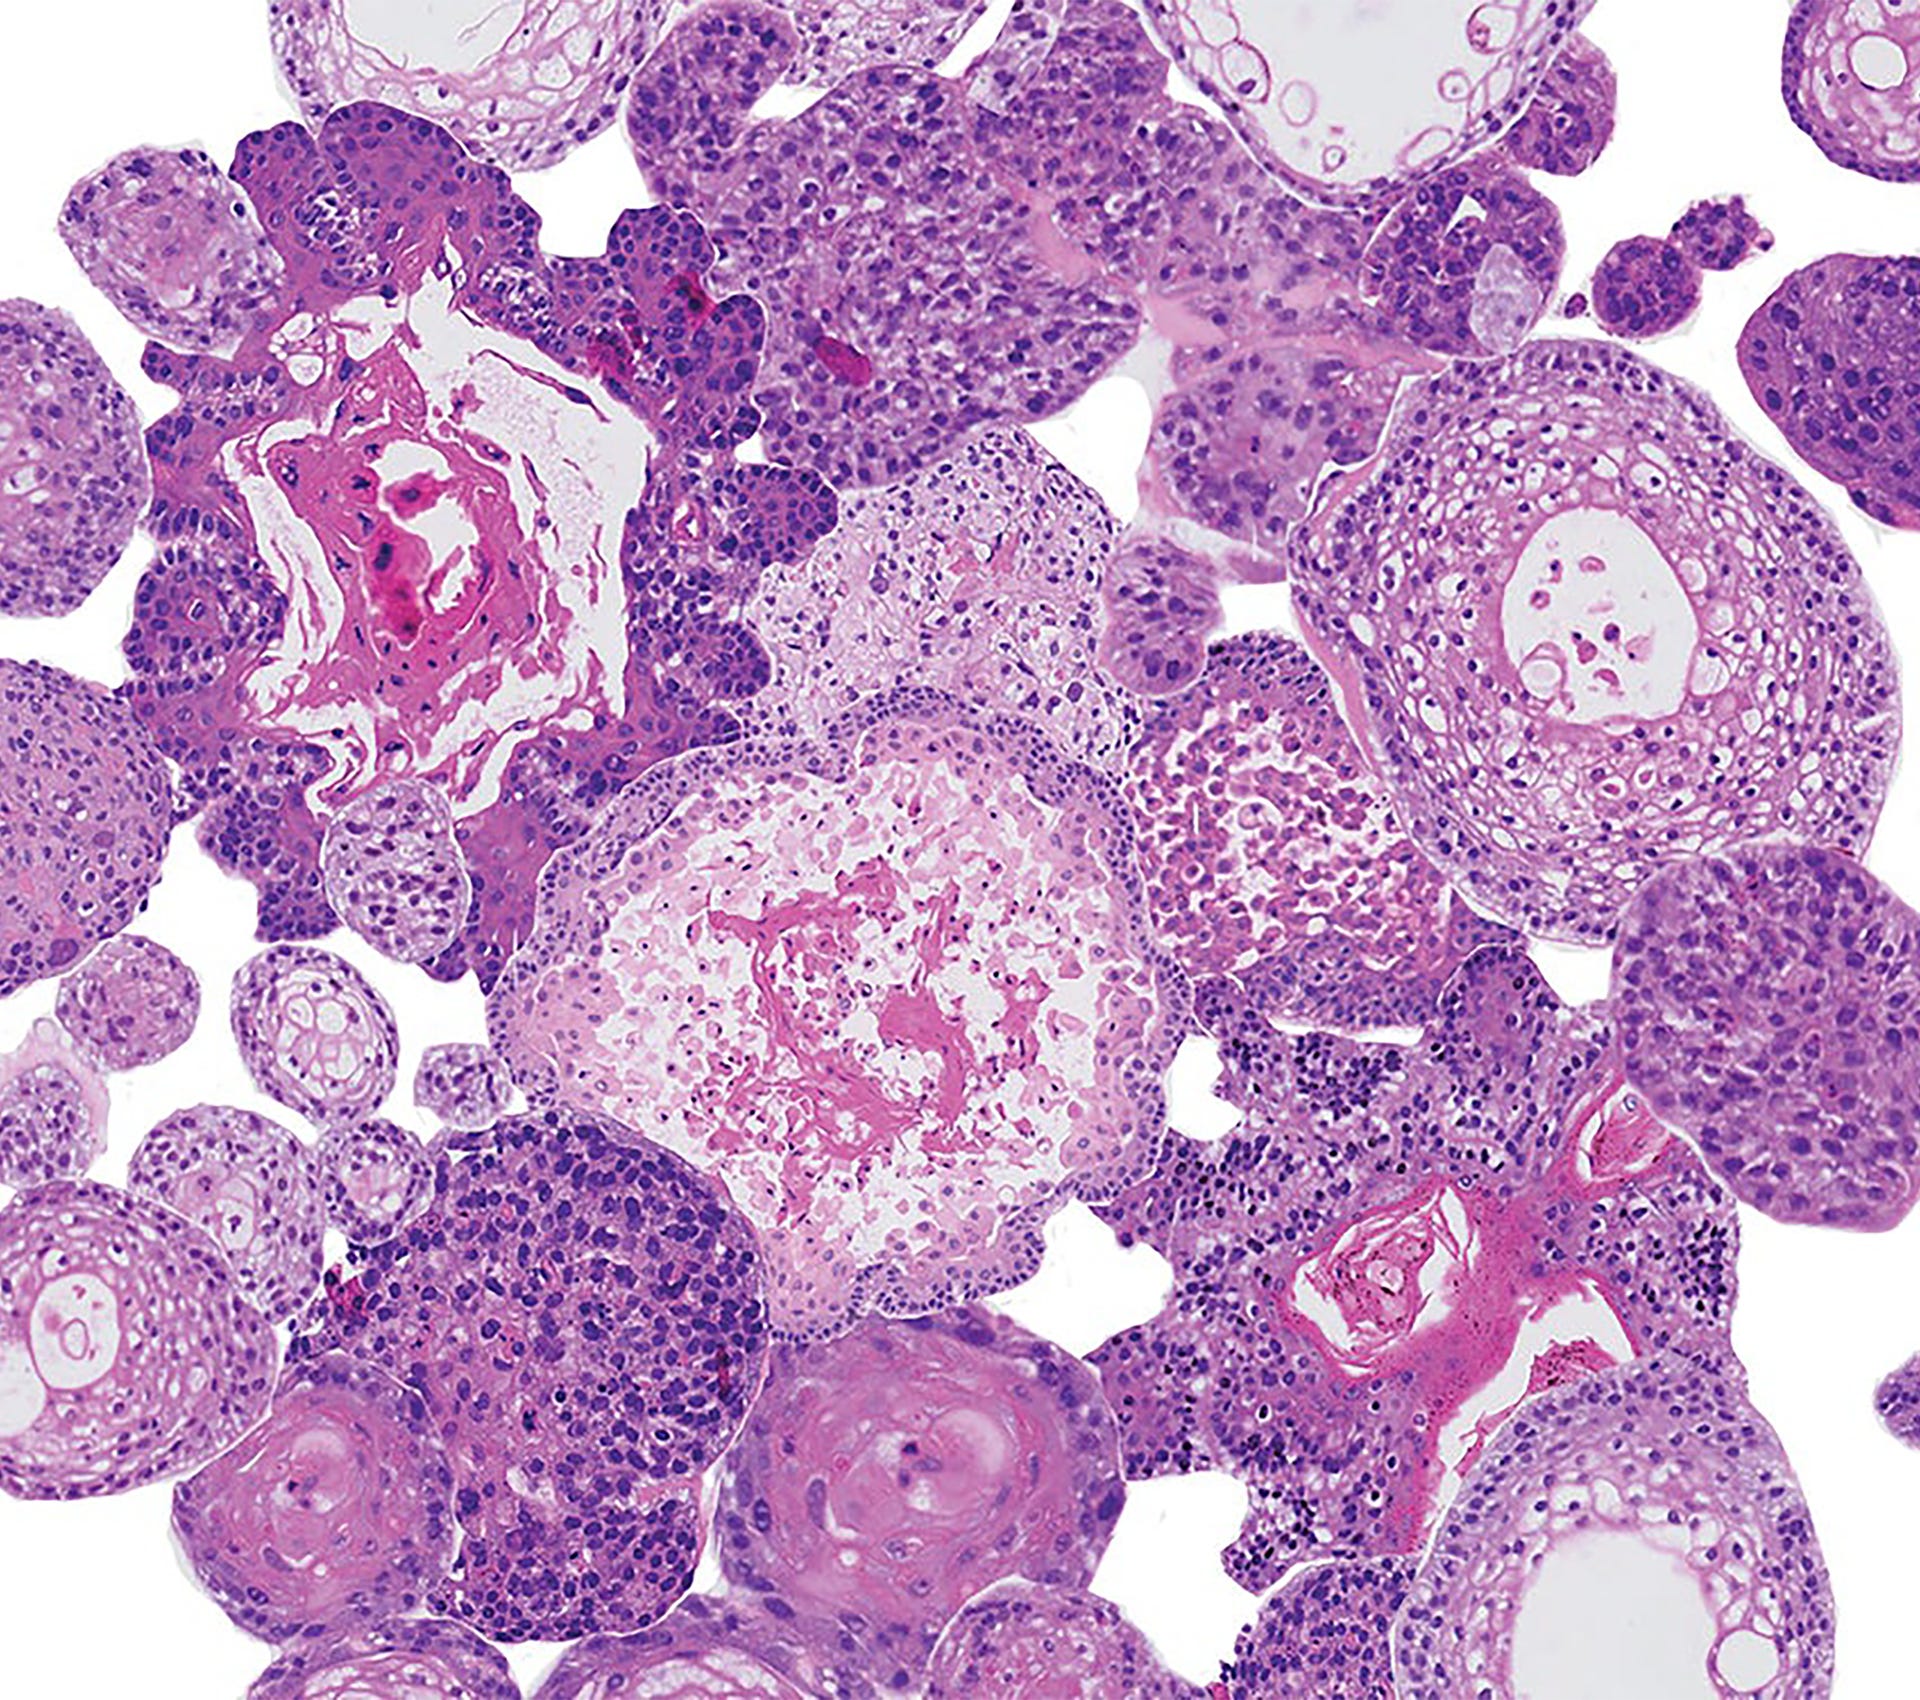

Een close-up van een microscoop; organoiden hoofd-halskanker